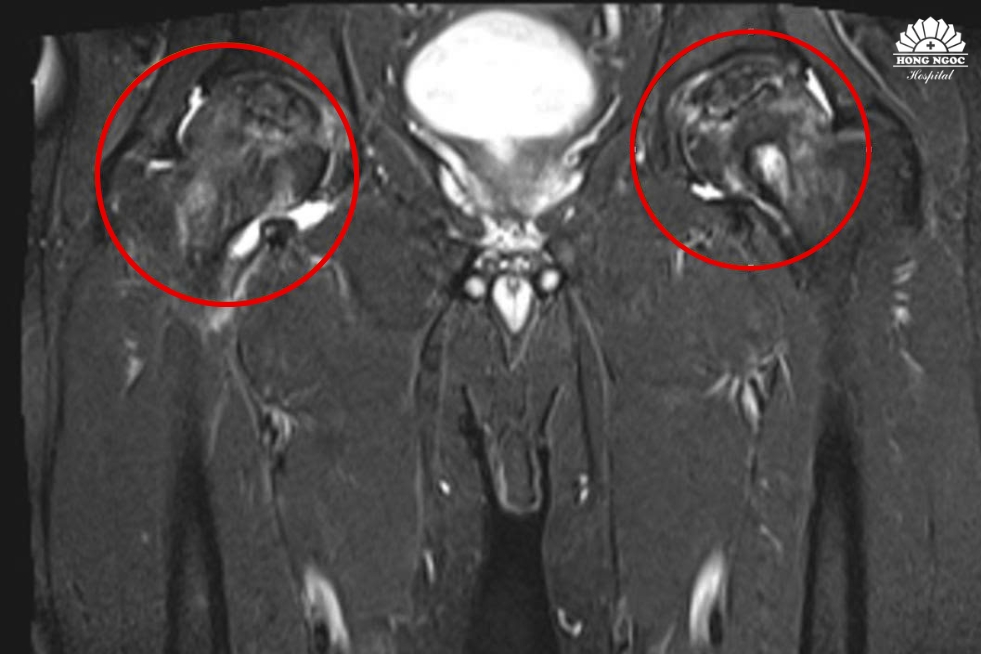

Hình ảnh khớp háng bị hoại tử

Ông T được chỉ định thay 2 khớp háng bằng phương pháp SuperPATH - phương pháp ít xâm lấn, phục hồi nhanh nhưng ông quyết định thực hiện thay khớp háng phải trước vì muốn đảm bảo sức khỏe. Theo TS.BS Lê Quang Huy, Trưởng khoa Ngoại Chấn thương chỉnh hình - Thần kinh sọ não, BVĐK Hồng Ngọc - Phúc Trường Minh: “Thông thường, bệnh nhân hoại tử khớp háng vô khuẩn (avascular necrosis) giai đoạn sớm sẽ không có triệu chứng hoặc đau nhẹ ở vùng khớp háng/bẹn, lan xuống đùi/mông. Giai đoạn muộn sẽ biểu hiện đau khớp háng khi nghỉ ngơi và đi lại khó khăn. Trường hợp bệnh nhân T phát hiện giai đoạn muộn là hiếm gặp, hình ảnh MRI cho thấy phần sụn khớp đã tổn thương độ III-IV không còn thích hợp để điều trị bảo tồn và khoan giảm áp, cần phải phẫu thuật thay khớp để cải thiện vận động. Chúng tôi lựa chọn phương pháp SuperPATH giúp loại bỏ phần chỏm xương đùi tổn thương, thay thế bằng khớp háng nhân tạo với đường mổ nhỏ chỉ khoảng 10 cm, ít xâm lấn, không cắt cơ. Bệnh nhân ít đau, tránh tình trạng tái trật khớp sau mổ, khôi phục khả năng vận động nhanh chóng.”